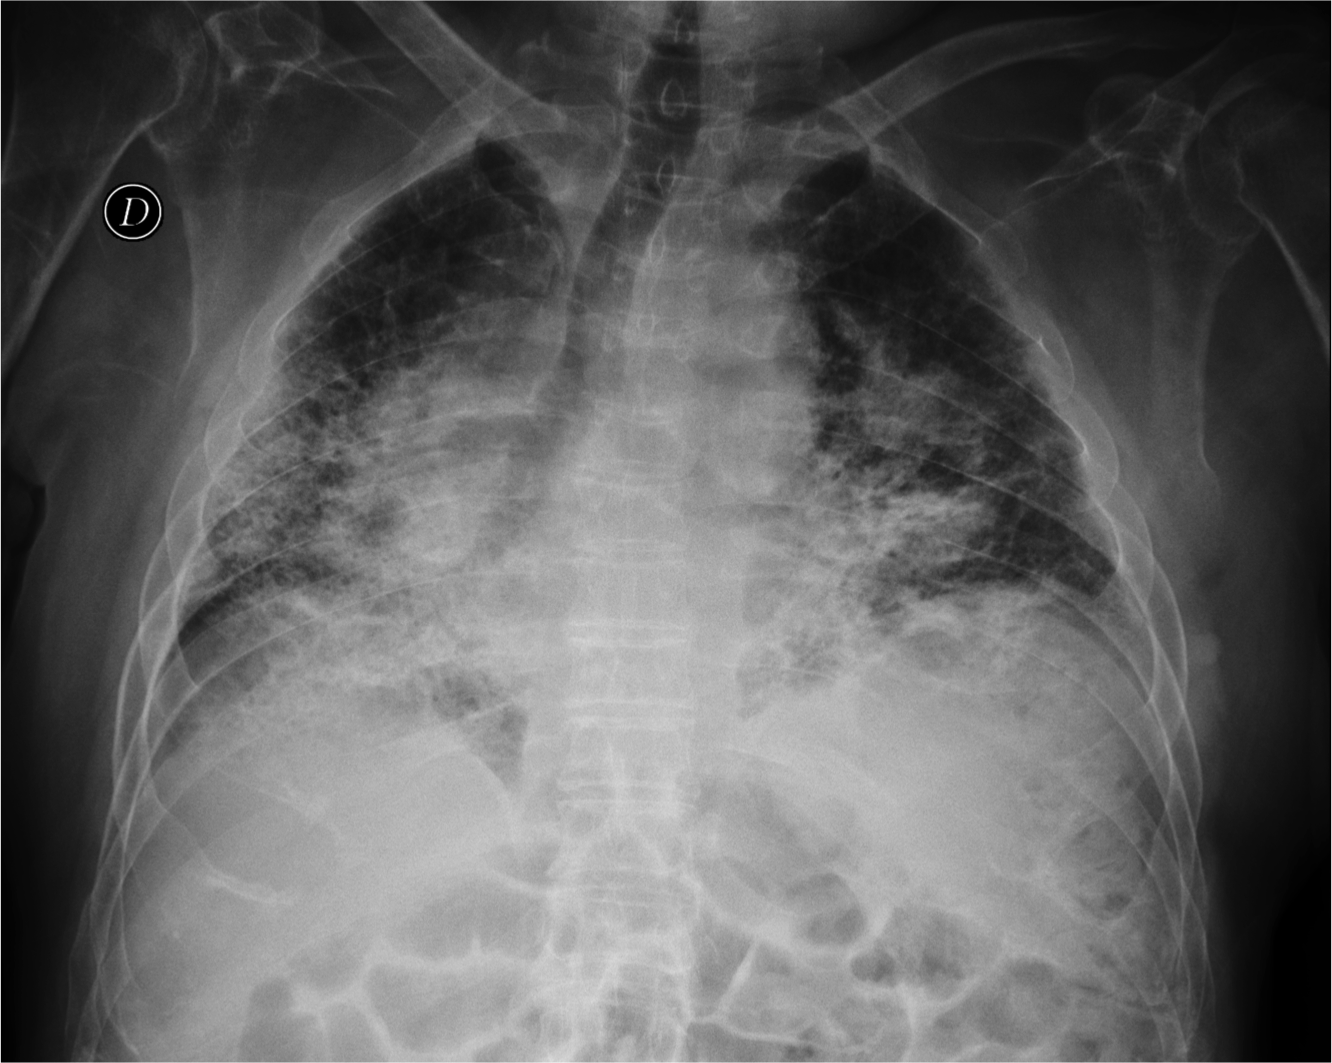

CASO: Paciente inmunodeprimido con Disnea.

Hallazgos:

- En la placa PA hay opacidad difusa bilateral de ambos hemitorax en vidrio deslustrado. En bases pueden intuirse opacidades mutifocales. La placa lateral también muestra la opacidad total del parénquima.

IMPORTANTE: Estos hallazgos son inespecíficos, pero ante un paciente inmunodeprimido, la evidencia de opacidad en forma de vidrio deslustrado, más aun si es de predominio perihiliar y en lóbulos superiores, hay que descartar en primer lugar una neumonía por Neumocistis, que en nuestro medio suele vincularse a pacientes VIH positivos.

VIDRIO DESLUSTRADO: Aumento de densidad difusa que no impiden la visualización de los vasos pulmonares que contienen. Se puede ver en afectación del espacio aéreo y/o del intersticio.

Causas:

- Infecciosas (P.Jiroveci y CMV)

- Neumonía intersticial descamativa.

- Alveolitis alérgica extrínseca.

- Sarcoidosis.

- Neumonía intersticial habitual.

- Proteinosis alveolar.

- Neumonía organizada criptogénica